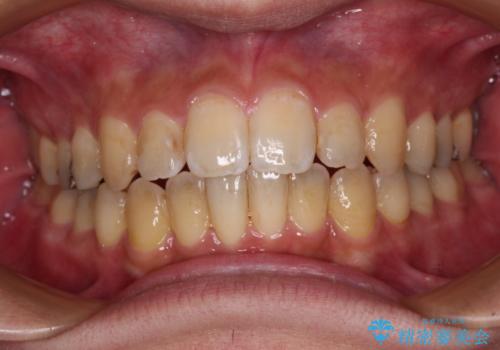

オープンバイトと目立つ銀歯 インビザライン矯正とセラミック修復治療

- 奥歯の目立つ銀歯と上下前歯の叢生と隙間を気にして来院された患者様です。

開咬の治療は、前歯を閉じるように動かすとともに、上下臼歯を圧下(骨内にめり込ませる)させることで進めて行きます。

インビザラインは臼歯の圧下を効果的に行えるため、インビザラインを用いて矯正治療を行うこととしました。

銀歯のセラミック治療が1番の希望であったため、ここまで歯列がきれいに整うとは思ってなかったようで、大変喜んでいただけました。